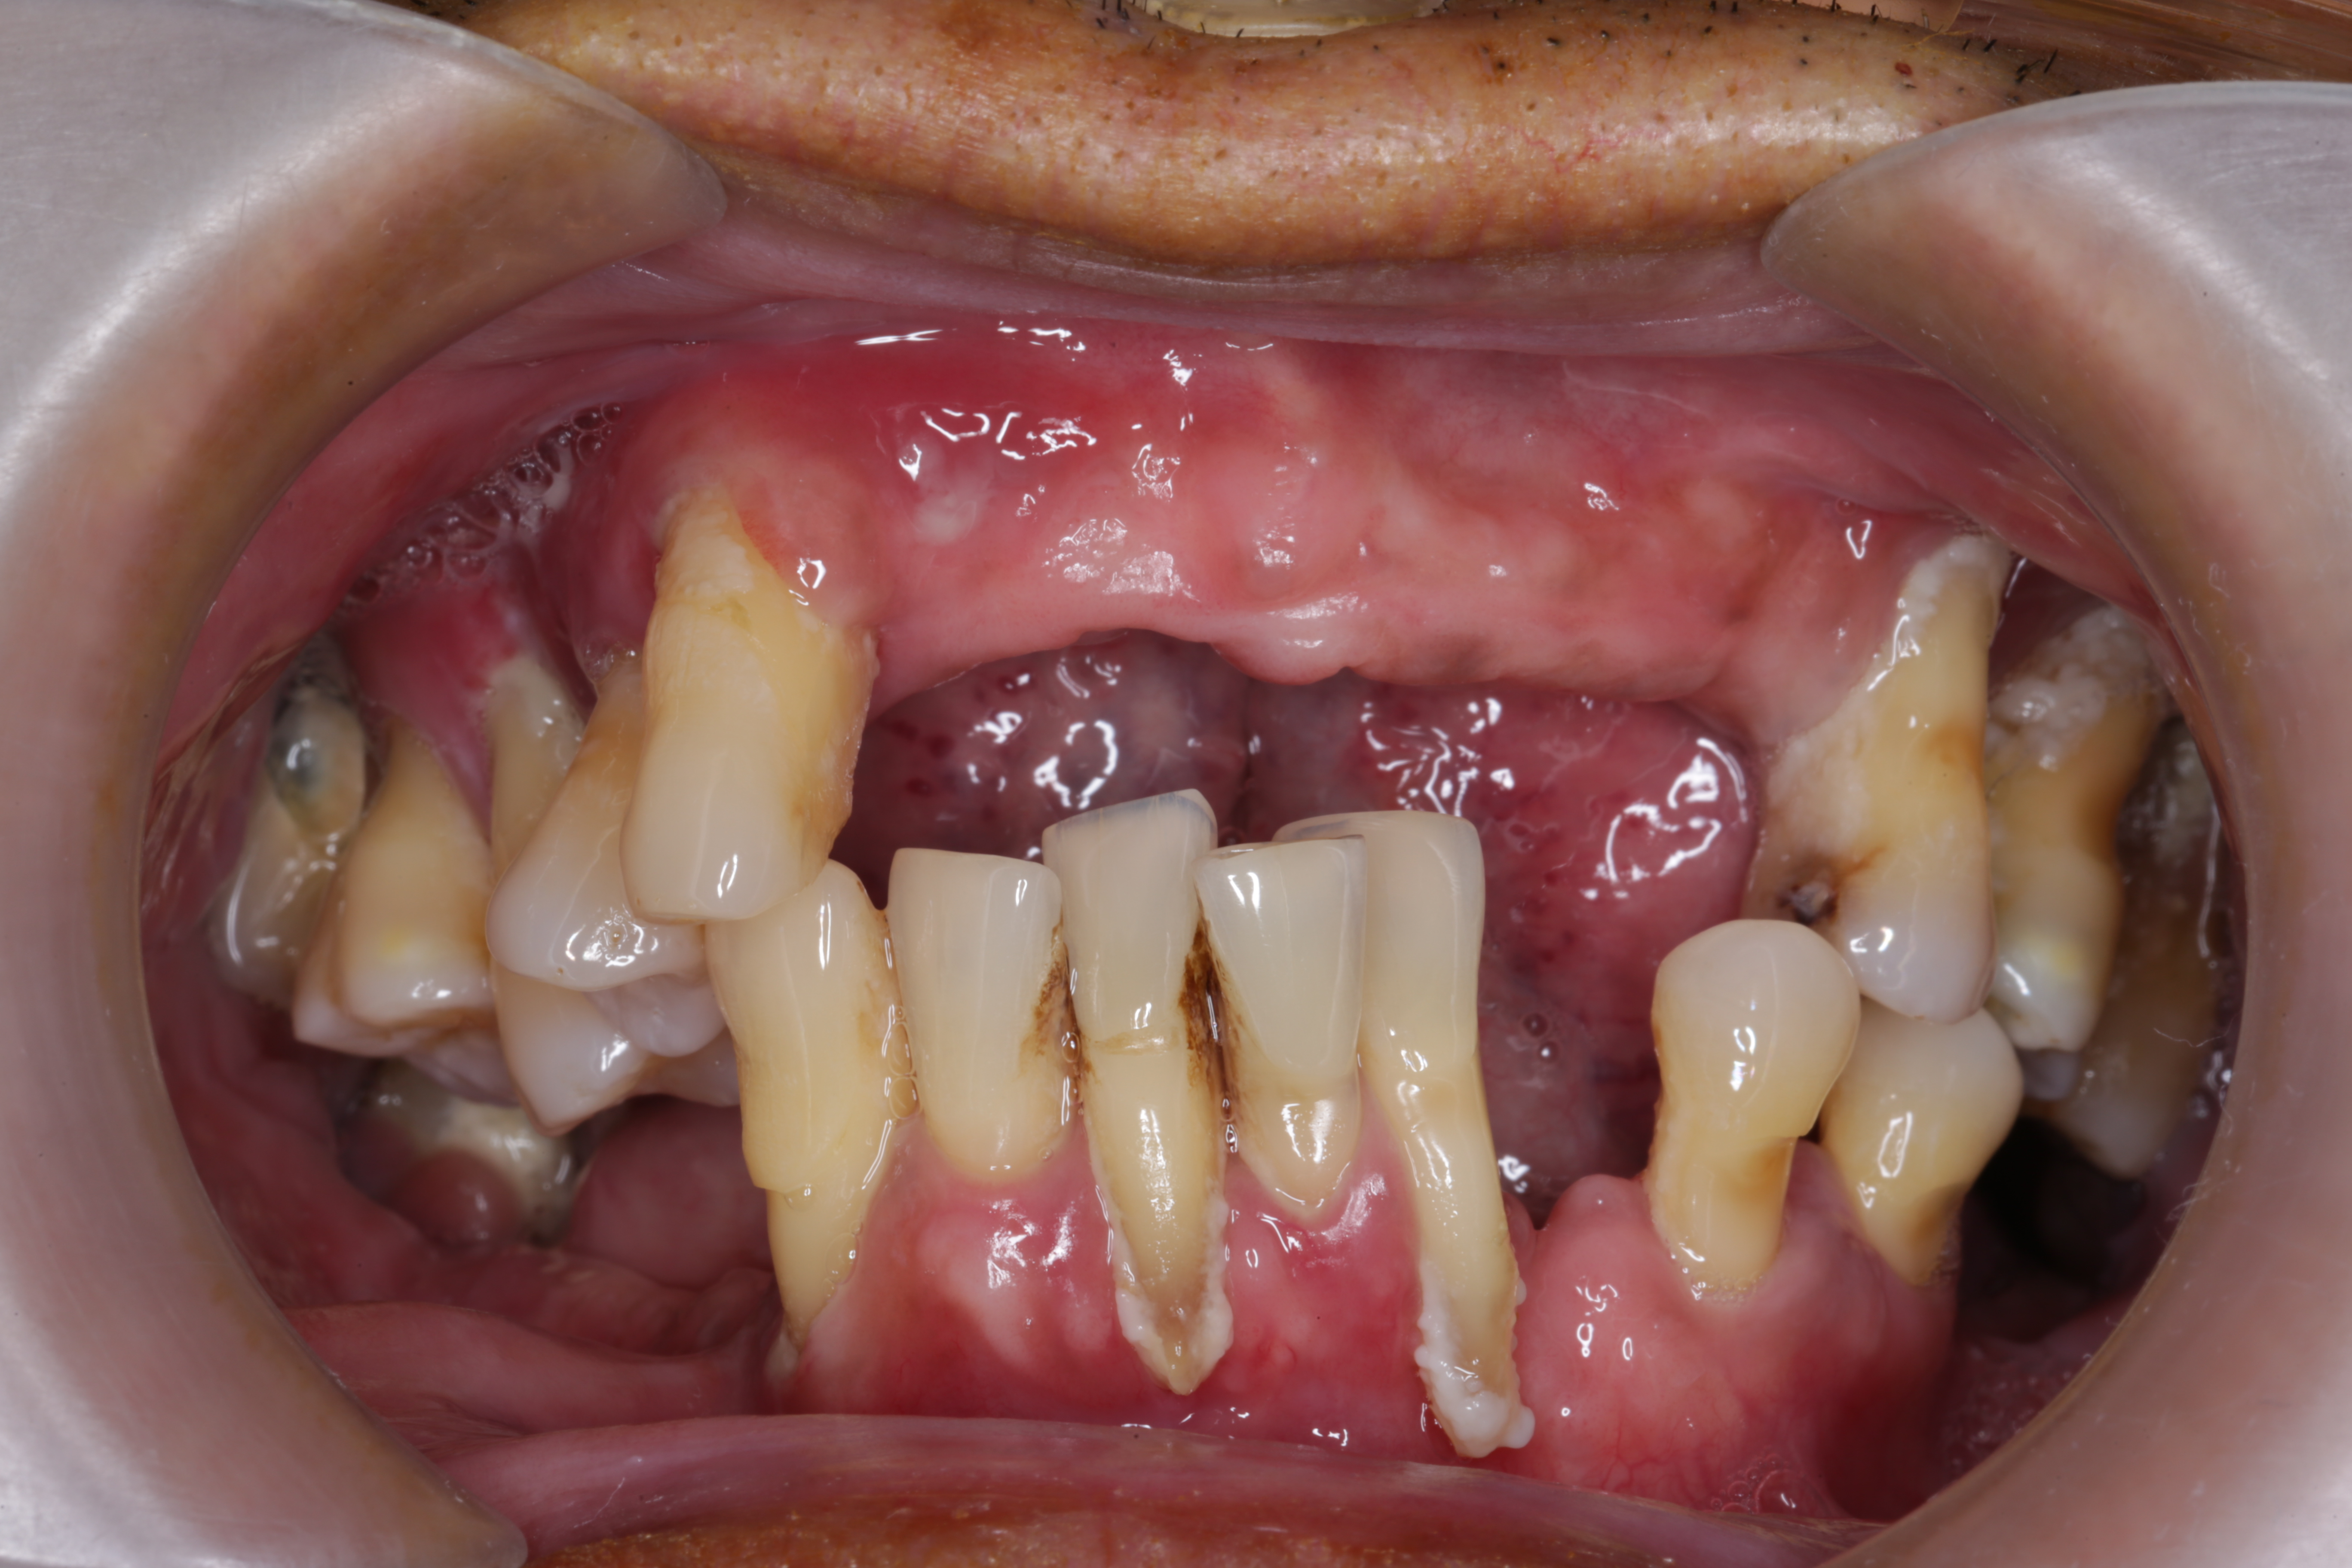

Viêm Nha Chu

Điều Trị Viêm Nha Chu